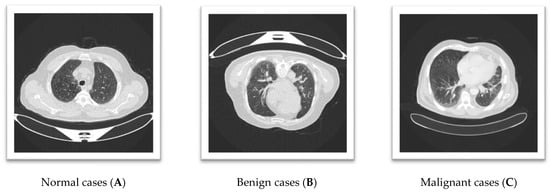

Figure 1 shows a lung CT scan image that reveals distinct findings for each case. Image A, representing a Normal case, shows a nodule or mass localized in the right lung, indicating a potential abnormality despite its classification as normal. Image B, classified as Benign, depicts clear lung fields with well-defined pulmonary vessels, consistent with non-pathological findings. Image C, labeled Malignant, exhibits interstitial changes or potential infiltrates in the lower lung fields, suggesting significant pathological alterations. These observations highlight the variability in CT scan presentations across different classifications, emphasizing the importance of accurate feature interpretation for reliable diagnosis.

Figure 1.

The three lung CT scan images.